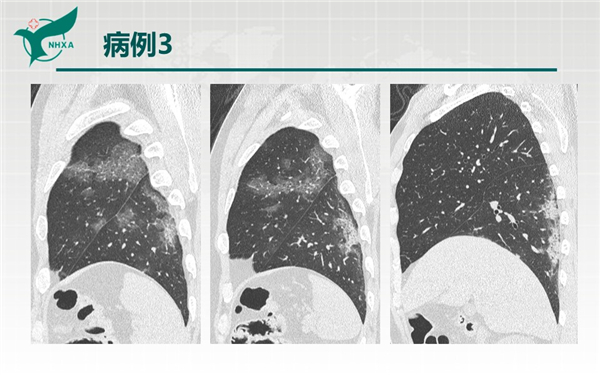

【病例分享】新型冠狀病毒肺炎3例(西安市第九醫(yī)院)

幻燈片10.jpg